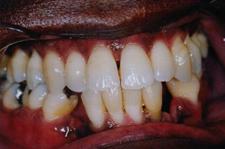

Parodontite moderate

dintii par alungiti datorita retractiei gingivale

pot apare abcese parodontale

halena

mobilitate dentara si diastemizare patologica

pungi parodontale de 4-6 mm

resorbtie osoasa

Parodontite severe

mobilitate dentara accentuata pâna la avulsia dintilor

migrari patologice

halena constanta

hiperestezie dentinara datorata denudarii radacinii

pungi parodontale > de 6 mm

resorbtie osoasa accentuata